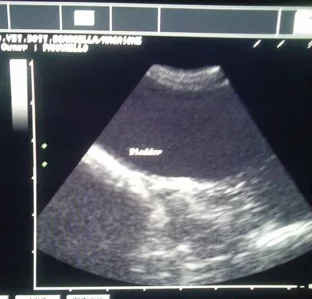

Svolgiamo attività di ecografia internistica e ci rivolgiamo a professionisti esterni nei casi ostici per offrire sempre un servizio di qualità ed avere uno stimolante confronto con i colleghi specialisti. Si eseguono inoltre su richiesta referti radiografici ed ecografici.